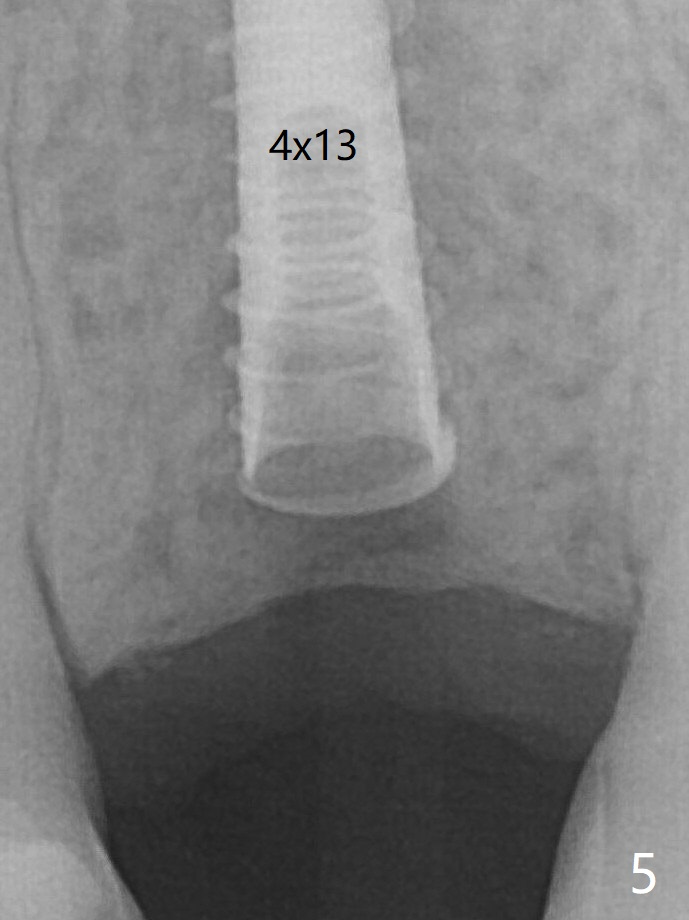

A 4x13 mm IBS implant is seated incompletely.  The osteotomy is further enlarged by 3.8 mm Magic Drill for 11 mm and deepened with 3 mm drill until 18 mm.  Finally the implant is placed at a satisfactory level with insertion torque > 50 Ncm (Fig.5).  The patient chooses to return for impression 6 months postop (Fig.6).  The abutment changes to a 4x4(4) mm one.  The crown is recemented  nearly 2 years post cementation, which is related to distal and deep placement of the implant and bruxism (Fig.7).